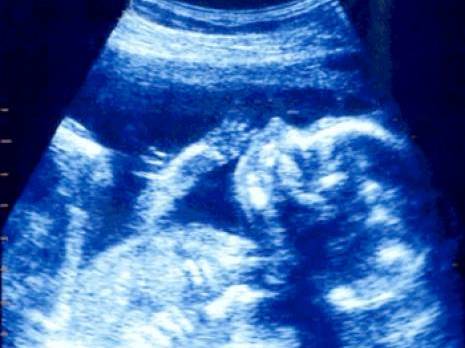

Les malformations f'tales constituent un sérieux problème de santé publique. Des maladies que les spécialistes algériens s'attellent à diagnostiquer précocement grâce à l'échographie. Un moyen efficace pour voir de près le f'tus et détecter les anomalies foetales dont 40 à 60% n'ont pas de causes réelles. A l'initiative des laboratoires Dar Al Dawa, les premières assises consacrées à ce thème se sont tenues le 16 janvier à Alger. Le débat a porté justement sur l'apport de l'échographie 3D dans la détection des malformations f'tales au cours du premier et deuxième trimestres de la grossesse. La conférence a été animée par le Dr Jean Philippe Bault qui a mis l'accent sur l'importance des techniques nouvelles de l'échographie pour un diagnostic précoce des malformations pour une prise en charge également précoce, «laquelle peut être faite in utero», précise le Pr Bendaoud, gynécologue à l'hôpital Parnet à Alger.

Elle signale que la prévalence des ces malformations varie entre 2,8 et 3% en Algérie, et les malformations neurologiques viennent en tête. Ce qui nécessite un programme de prévention et une prise en charge dès la naissance du bébé. Le Pr Bendaoud a mené une étude dans le cadre de sa thèse sur un échantillon de 192 bébés à Alger et les résultats de cette enquête ont montré que 54% des ces f'tus sont décédés avant la naissance et 32% juste après. Par contre, un suivi a été assuré à 82 bébés nés avec des malformations actuellement pris en charge.